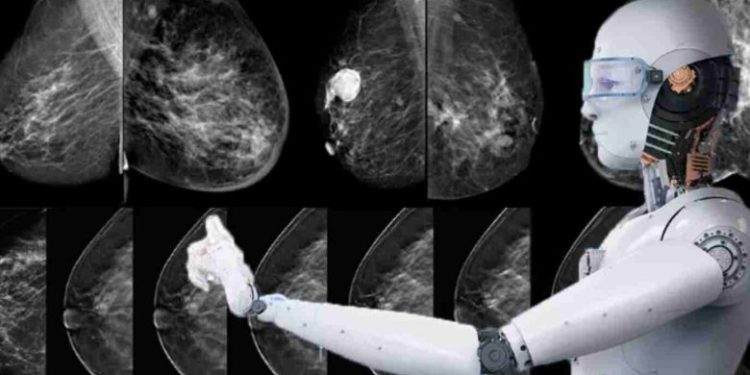

در این مقاله، یک سیستم تشخیص کامپیوتری هوشمند با الهامگرفتن از رفتار گرگهای خاکستری در شکارکردن و رفتار کرمهای شبتاب برای تشخیص سرطان ارائه شده است.

در این مقاله برای تشخیص سرطان از تصاویر حرارتی و ترکیب دو الگوریتم برگرفته از رفتار گرگهای خاکستری و کرمهای شبتاب استفاده شده است. استفاده از ترکیب این دو الگوریتم امکان دستیافتن بهدقت مناسب در تشخیص و استفاده از تصاویر حرارتی امکان تشخیص زودهنگام سرطان را فراهم آورده است.

در این مقاله، برای دستهبندی تصاویر حرارتی به دودسته تصاویر دارای توده سرطانی و تصاویر بدون توده سرطانی از الگوریتمهای دستهبندی kNN، SVM و DTree استفاده شده است.

نتایج شبیهسازیها نشان میدهد که استفاده از سیستم تشخیص کامپیوتری هوشمند پیشنهادی باعث افزایش دقت در تشخیص زودهنگام سرطان در تصاویر حرارتی در مقایسه با سایر کارهای انجام شده قبلی میشود.